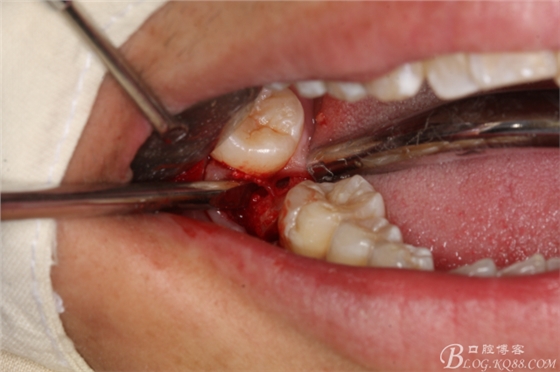

圖13.高速拔牙手機(jī)離斷舌側(cè)牙冠

圖14.挺出47舌側(cè)部分牙冠

圖15.梃子放頰側(cè),以頰側(cè)骨板做支點(diǎn)。挺松47牙根。